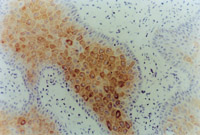

MEBT/MEBO治療30天后,再生修復(fù)的上皮組織進(jìn)行細(xì)胞角質(zhì)素AE3檢查為陽性,表皮顆粒層細(xì)胞質(zhì)呈棕色染色,細(xì)胞核呈藍(lán)色(圖5-3-9~5-3-6),證實為自身再生的復(fù)層鱗狀上皮。

5-3-9 MEBT/MEBO治療30天,細(xì)胞角質(zhì)素AE3呈陽性。(說明患者燒傷創(chuàng)面是自我再生修復(fù)) HE×20

5-3-10 同上  HE×40